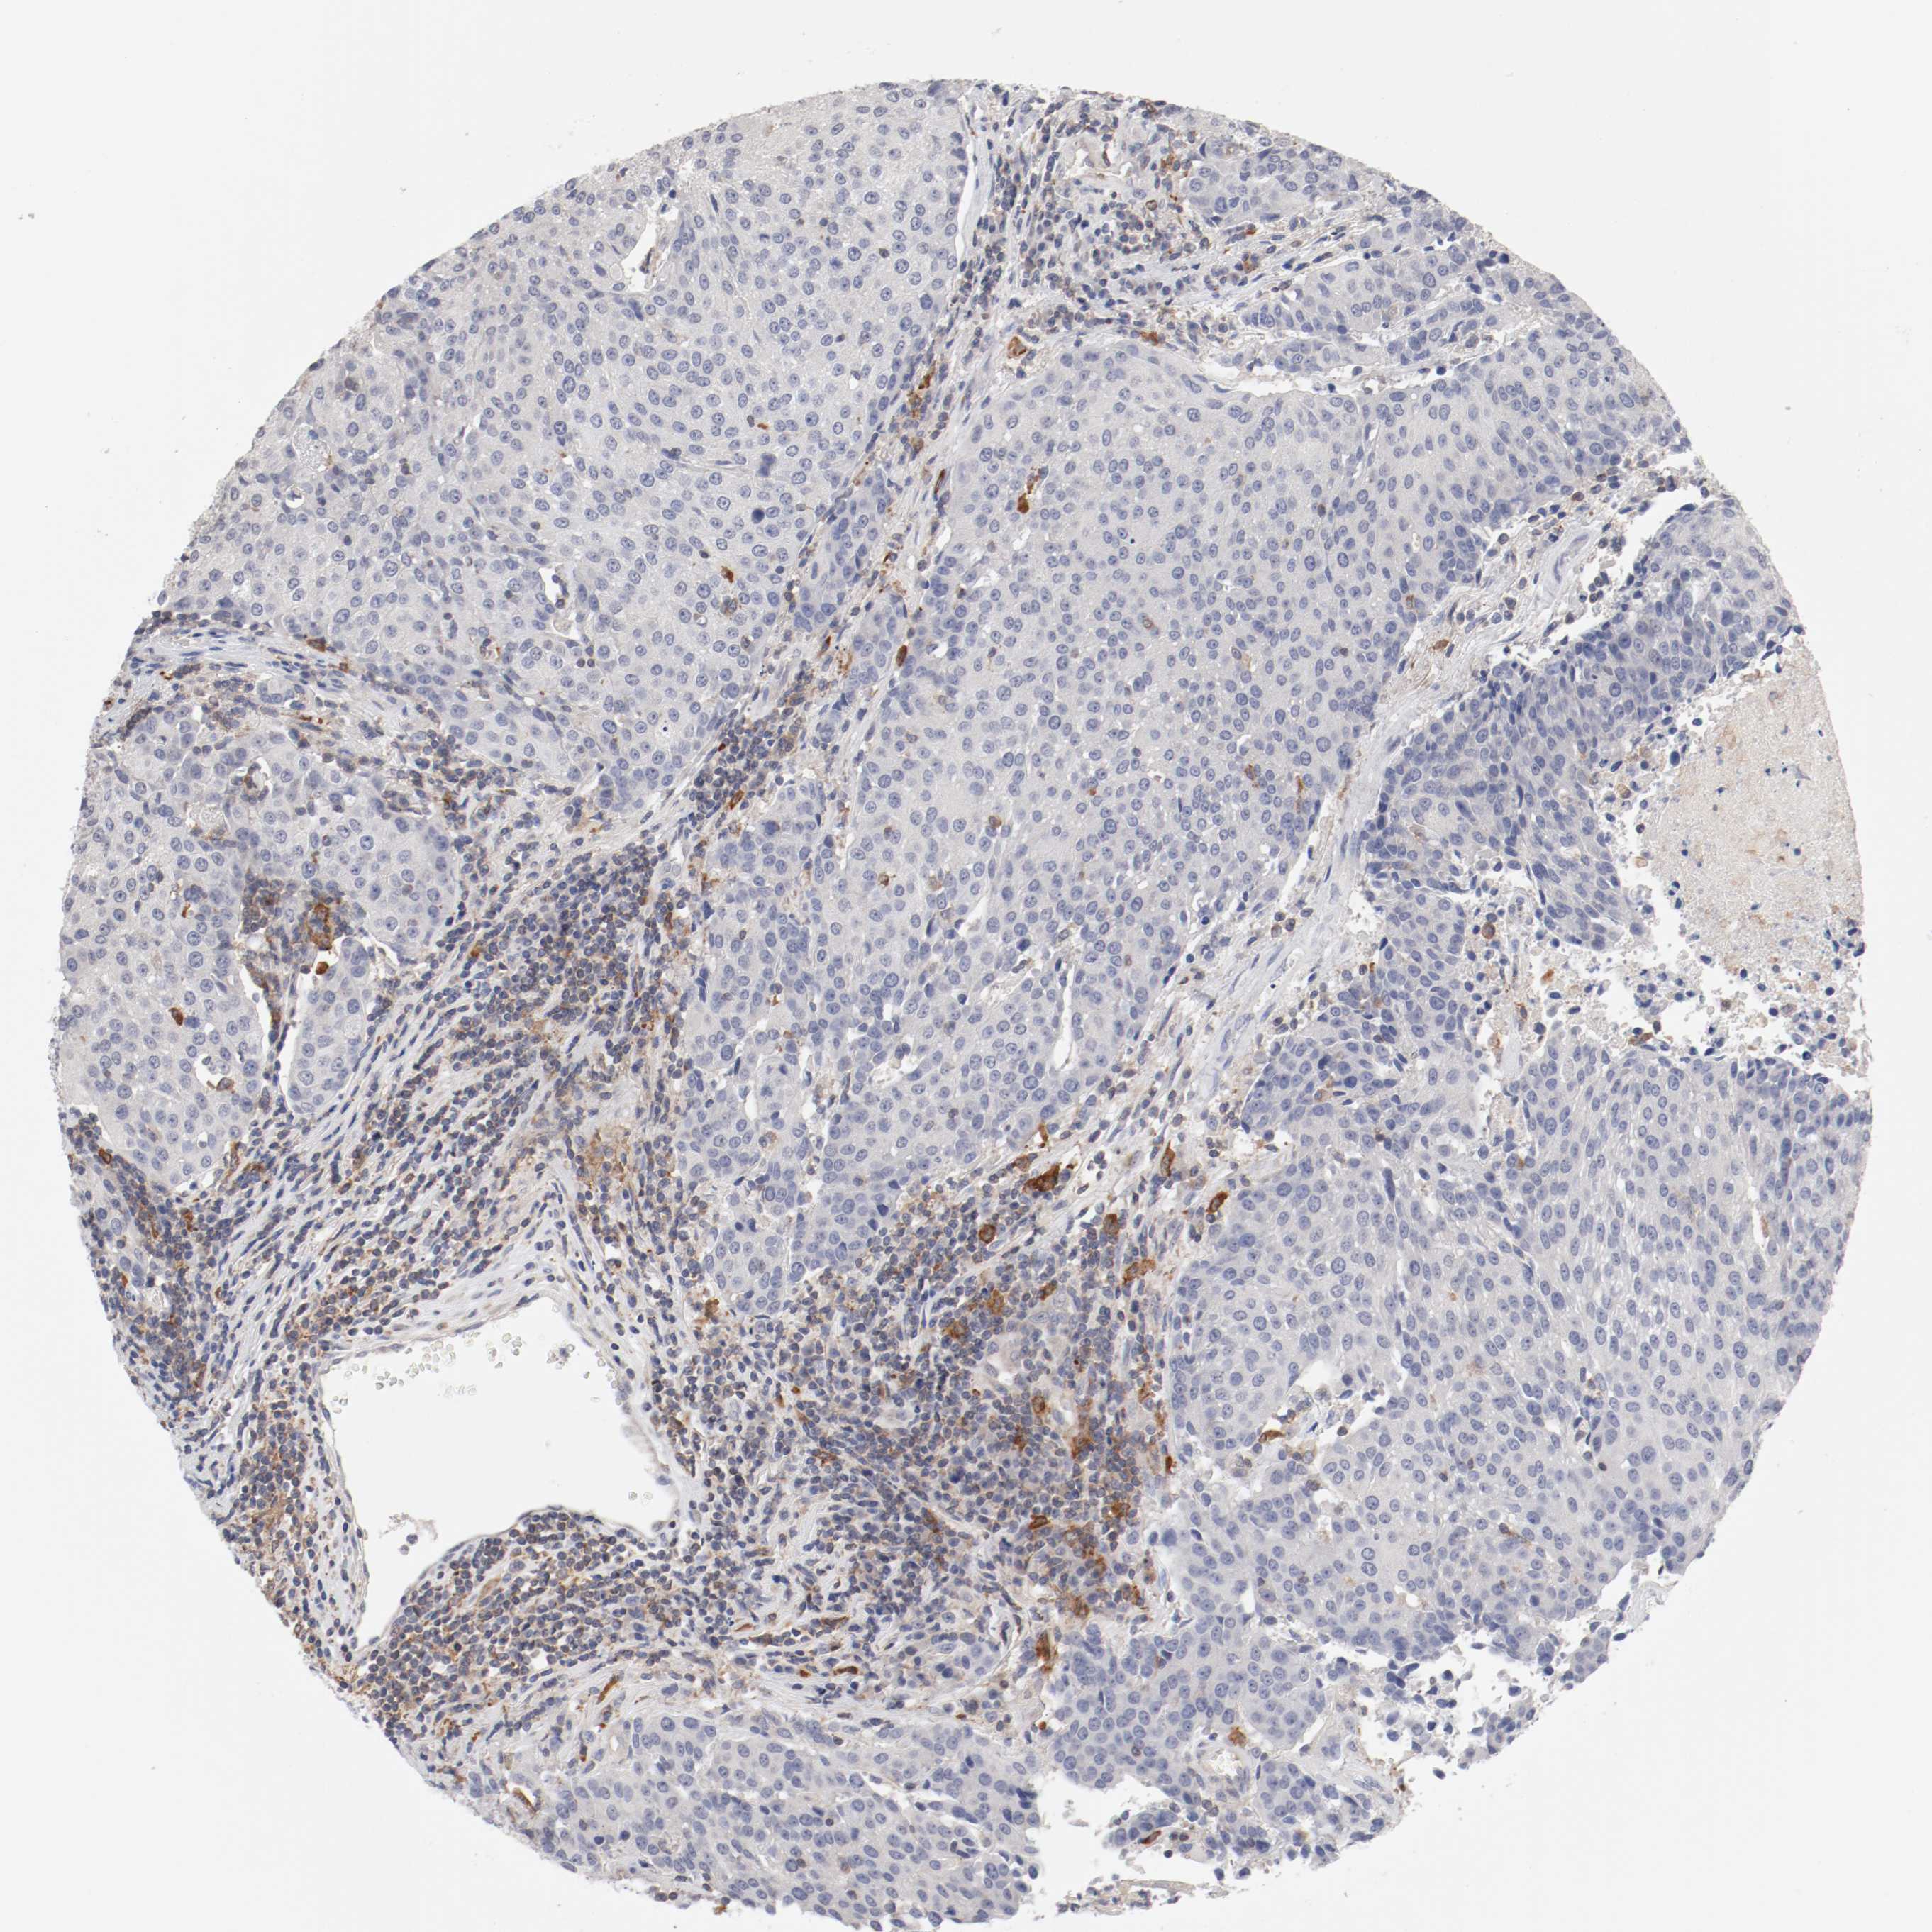

UROTHELIAL CANCER - Protein expressioni

A mouse-over function shows sample information and annotation data. Click on an image to view it in a full screen mode. Samples can be filtered based on level of antibody staining by selecting one or several of the following categories: high, medium, low and not detected. The assay and annotation is described here.

Antibody stainingi

Antibody staining in the annotated cell types in the current human tissue is reported as not detected, low, medium, or high, based on conventional immunohistochemistry profiling in selected tissues. This score is based on the combination of the staining intensity and fraction of stained cells.

Each image is clickable and will lead to virtual microscopy that enables deeper exploration of all samples and also displays staining intensity scores, fraction scores and subcellular localization as well as patient and tissue information for each sample.

Antibody HPA027956

Antibody CAB004350

Staining

High

Medium

Low

Not detected

Intensity

Strong

Moderate

Weak

Negative

Quantity

>75%

75%-25%

<25%

None

Location

Nuclear

Cytoplasmic/membranous

Cytoplasmic/membranous,nuclear

Urothelial carcinoma, Low grade

Urothelial carcinoma, High grade